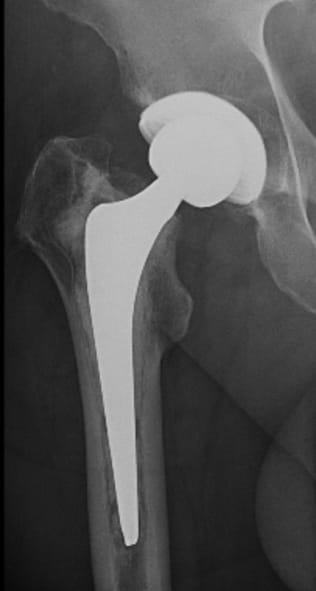

Mr J underwent a total hip replacement outside London 6 years ago. He had been suffering pain for over a year and noticed that his leg had shortened by over a centimetre. Investigations revealed he had a non-infective loosening of the original hip replacement stem. He underwent successful revision surgery under the care of Mr Simon Newman.

Mr Newman said “For most people undergoing hip replacement, one operation is all they will need. However, if problems do arise, then modern implant technology and surgical techniques have made revision hip replacement surgery a safe effective option.”